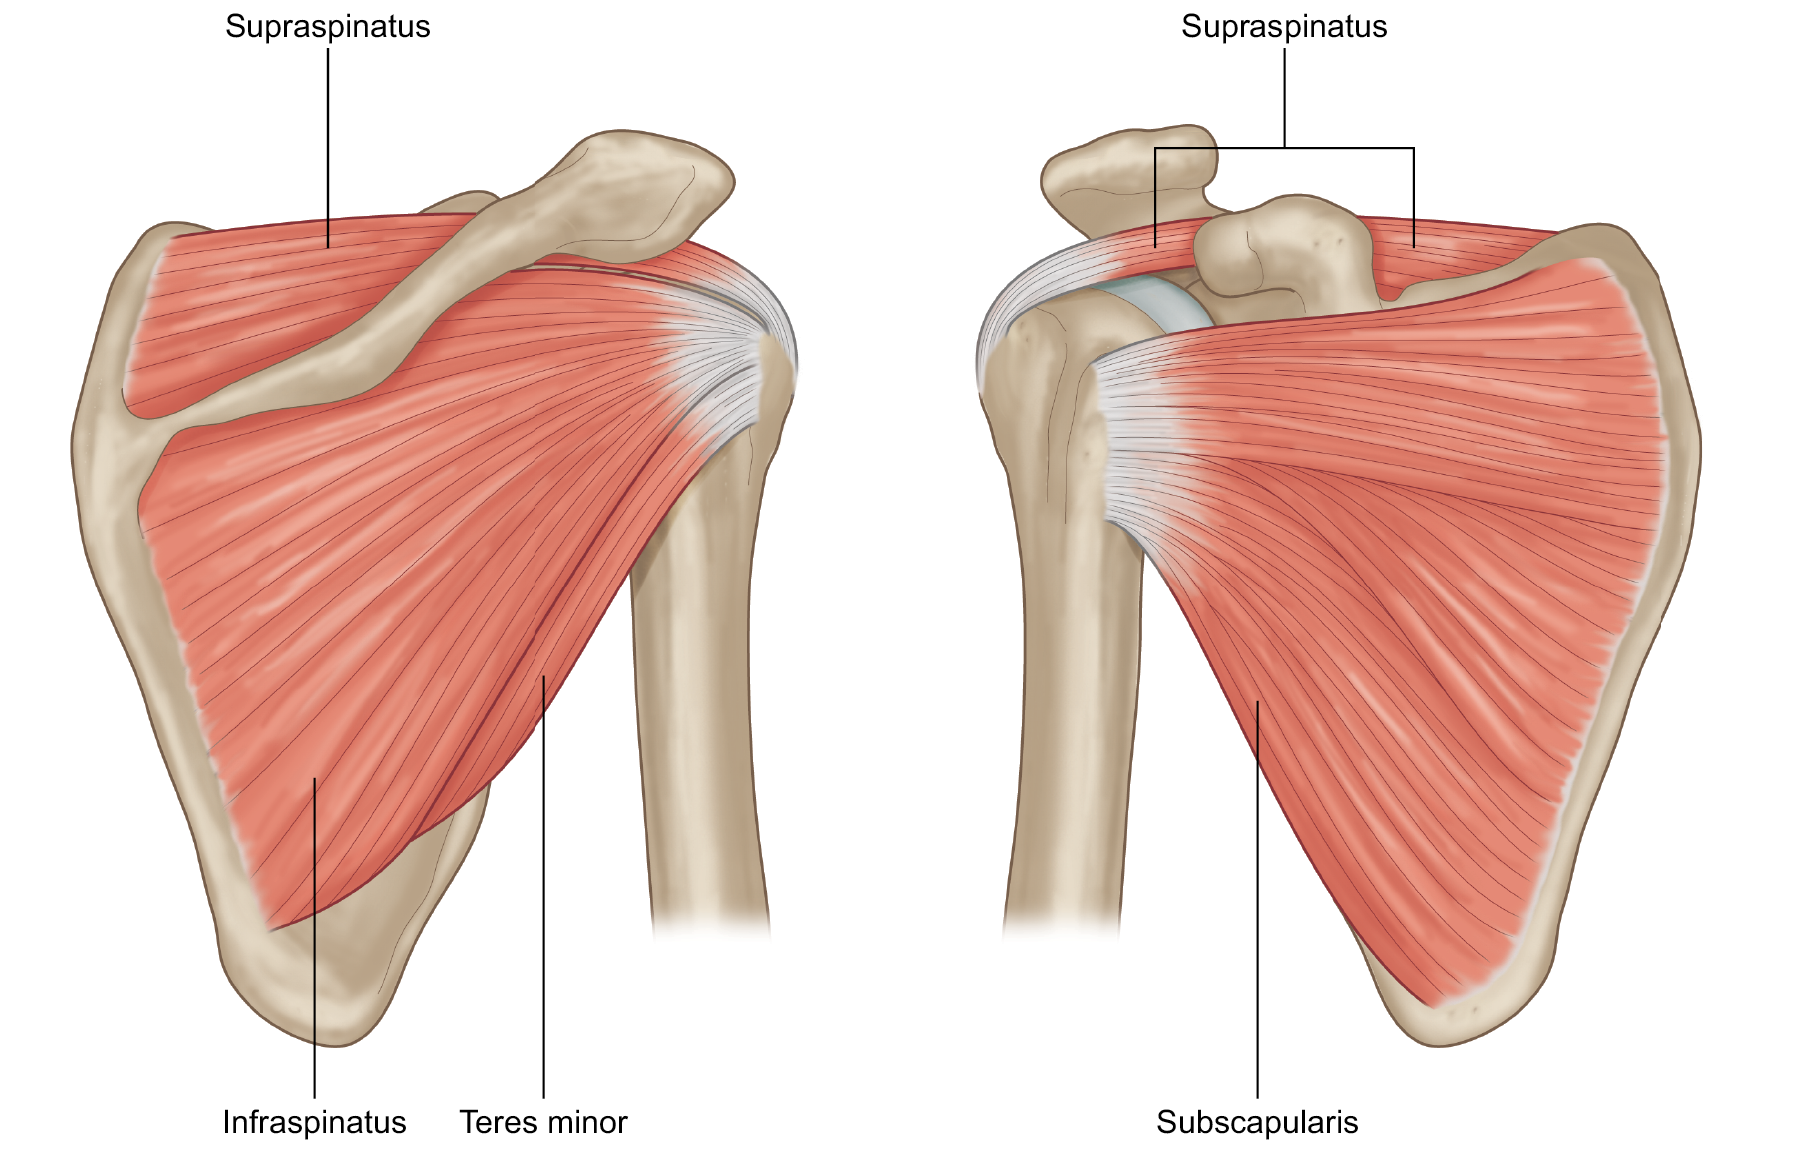

Фотографии мышц ротаторной манжеты плеча